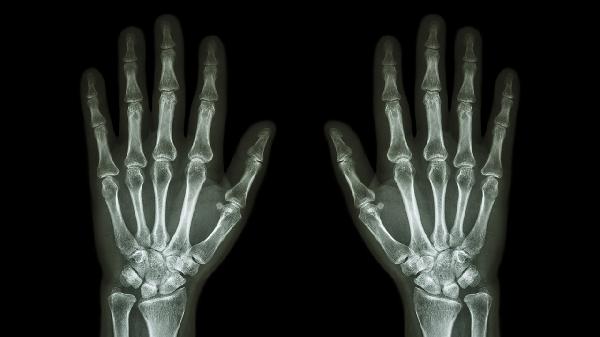

甲状旁腺功能亢进、肾性骨营养不良等疾病可导致骨代谢紊乱。患者可能出现全身骨痛、肌肉无力、病理性骨折等症状。代谢异常导致的骨折常见于肋骨、骨盆等部位。治疗需针对原发病,如控制血钙水平、改善肾功能等。定期监测骨代谢指标很重要。